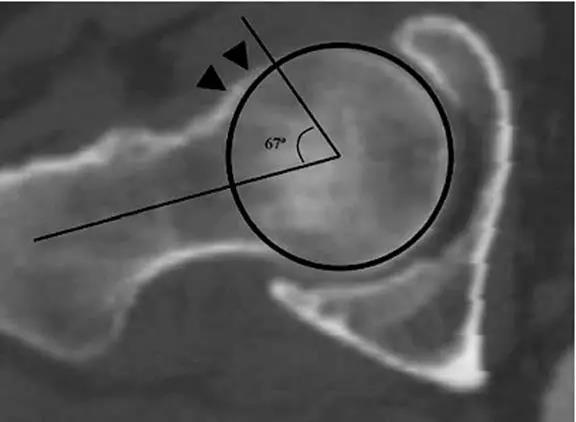

- 股骨头中心O点为圆心,股骨头正常最大半径为r,从股骨头颈连接处骨质与这个圆的交点(A点)到股骨头中心点作直线OA,此直线与股骨颈中轴线OB的交角为α角。

- 反映股骨颈骨赘突出程度,α角越大,越容易发生前上方股骨头颈与髋臼唇的撞击。

- FAI组中该角平均为74.0°±5.4°,正常对照组为42.0°±2.2°。

- α角>50°是诊断FAI的临界值。

- 股骨头颈联合处前缘骨性突起、骨质硬化,α角增大。